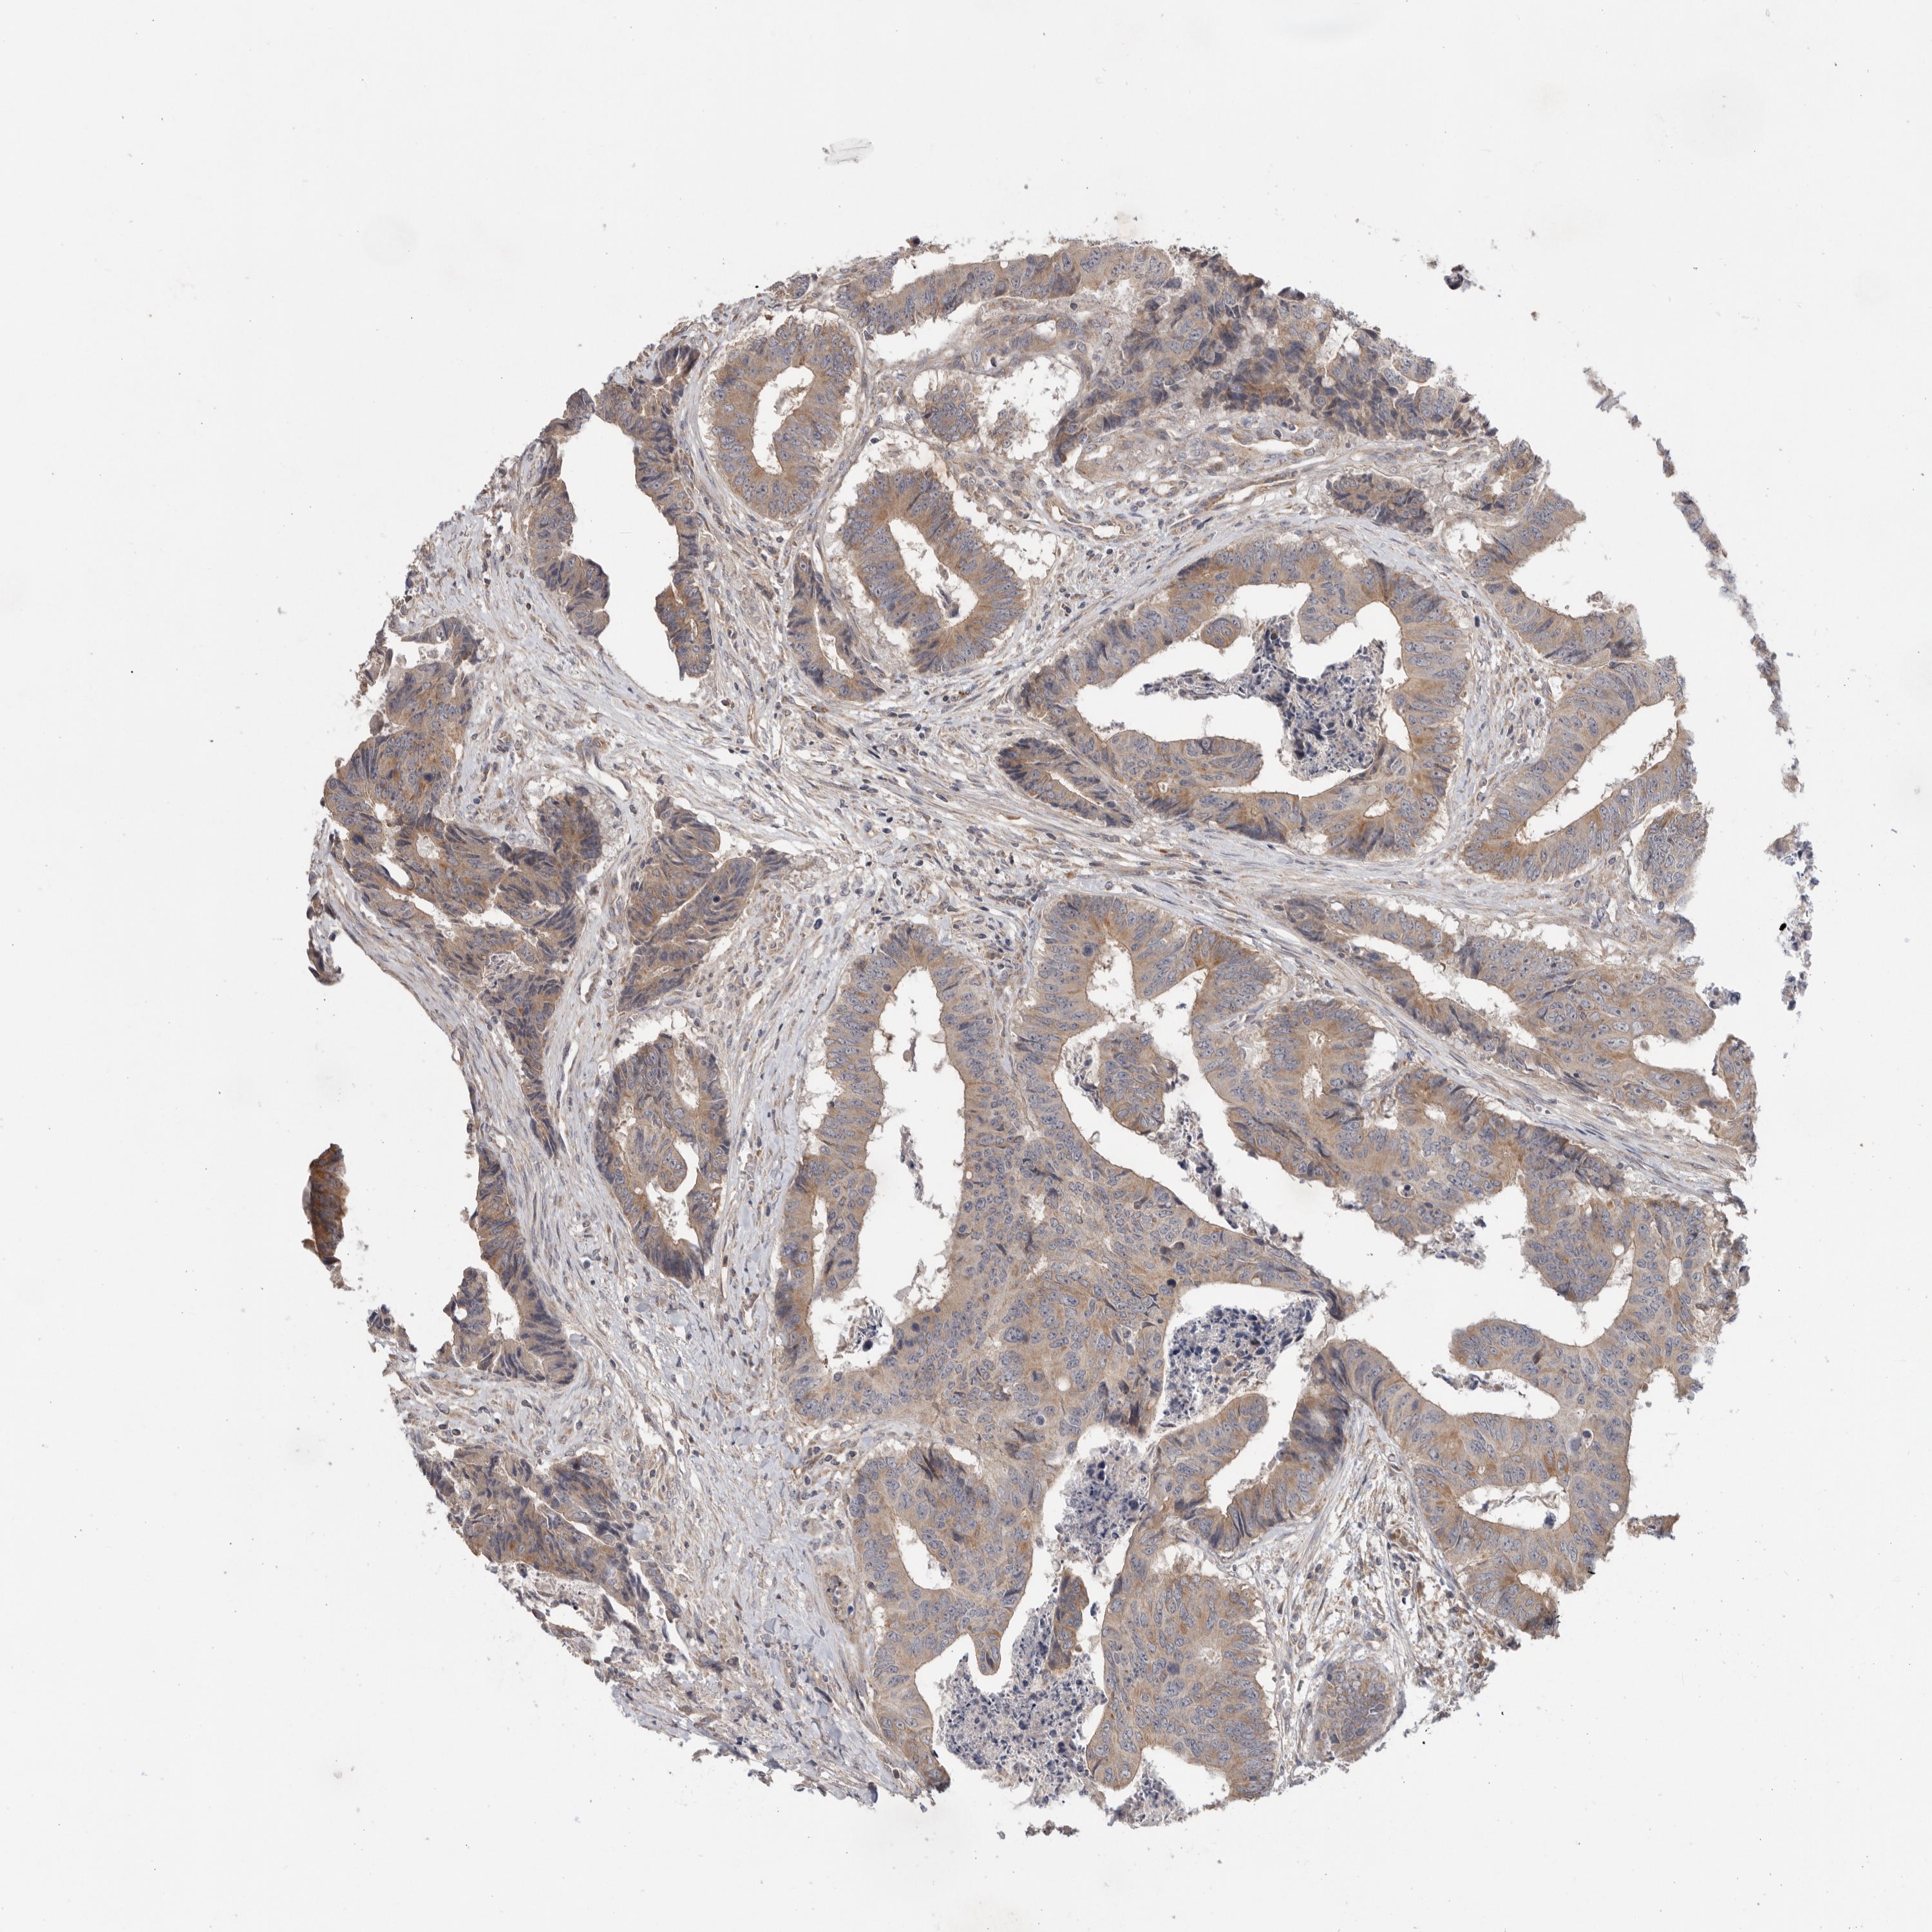

Colorectal cancer

Colon adenocarcinoma